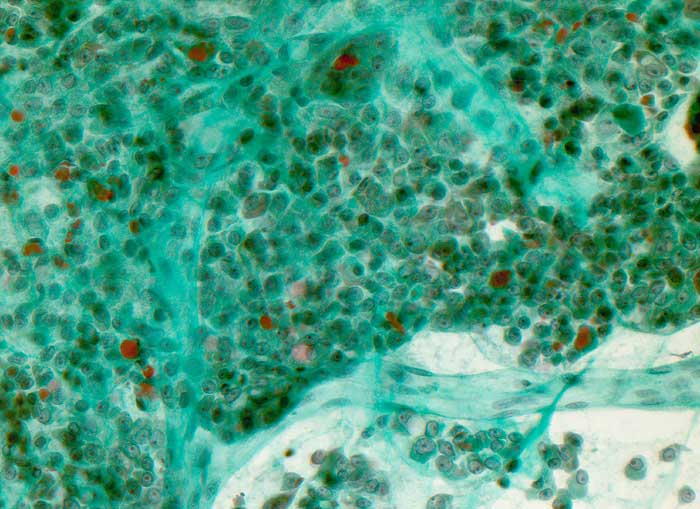

onkozytäre mikrofollikuläre Neoplasie

Massenhaft onkozytäre Zellen mit relativ breitem Zytoplasma und unterschiedlich grossen Kernen. Sie enthalten einen besonders auffälligen grossen Nukleolus. Die onkozytären Zellen bilden oftmals kleine mikrofollikuläre Strukturen und sitzen verzweigten fibrovaskulären Achsen auf.

Histologische Diagnose: Minimal invasives onkozytäres Karzinom der Schilddrüse. Herdförmige einzelne Tumoreinbrüche in kleine Gefässe der Tumorkapsel. Umschriebene Kapselarrosion. pT3

Zytologische Diagnose: Massenhaft Zellen und Zellverbände einer onkozytären Neoplasie mit Kernatypien.

Die Zellatypien, insbesondere die ungewönlich grossen Nukleolen sind suspekt auf ein onkozytäres Karzinom. Eine sichere Unterscheidung zwischen einem onkozytären Karzinom und einem onkozytären Adenom mit Atypien ist aber nicht möglich.